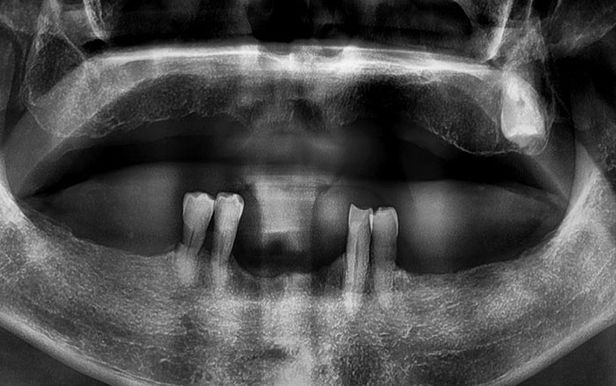

위아래 틀니를 사용하다 무절개 임플란트로 새로운 치아를 갖게 된 엑스레이 전과 후 모습.